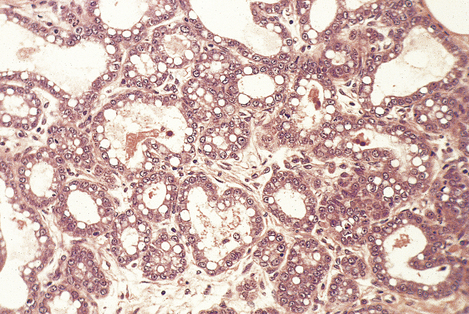

Mucinous carcinomas

Mucinous carcinomas (also known as colloid, mucoid and gelatinous carcinomas) usually arise in post-menopausal women and comprise 2–3% of invasive carcinomas.

Macroscopically, the tumours are well circumscribed and have a soft, grey, gelatinous cut surface. They vary in size from 10 to 50 mm in diameter. Since there is no dense stroma and the edges are rounded, these tumours do not cause retraction of the nipple or tethering of the skin.

These carcinomas comprise small nests and cords of tumour cells, which show little pleomorphism, embedded in large amounts of mucin (Fig. 18.24). The latter is composed of neutral or weakly acidic glycoproteins, which are secreted by the tumour cells and are different from the proteoglycans of the stroma.

image

Fig. 18.24 Mucinous carcinoma. Small solid and tubular groups of cells lie in pools of mucin, or jelly-like material.

The survival of women with mucinous carcinomas is better than that of those having invasive duct or lobular carcinomas.